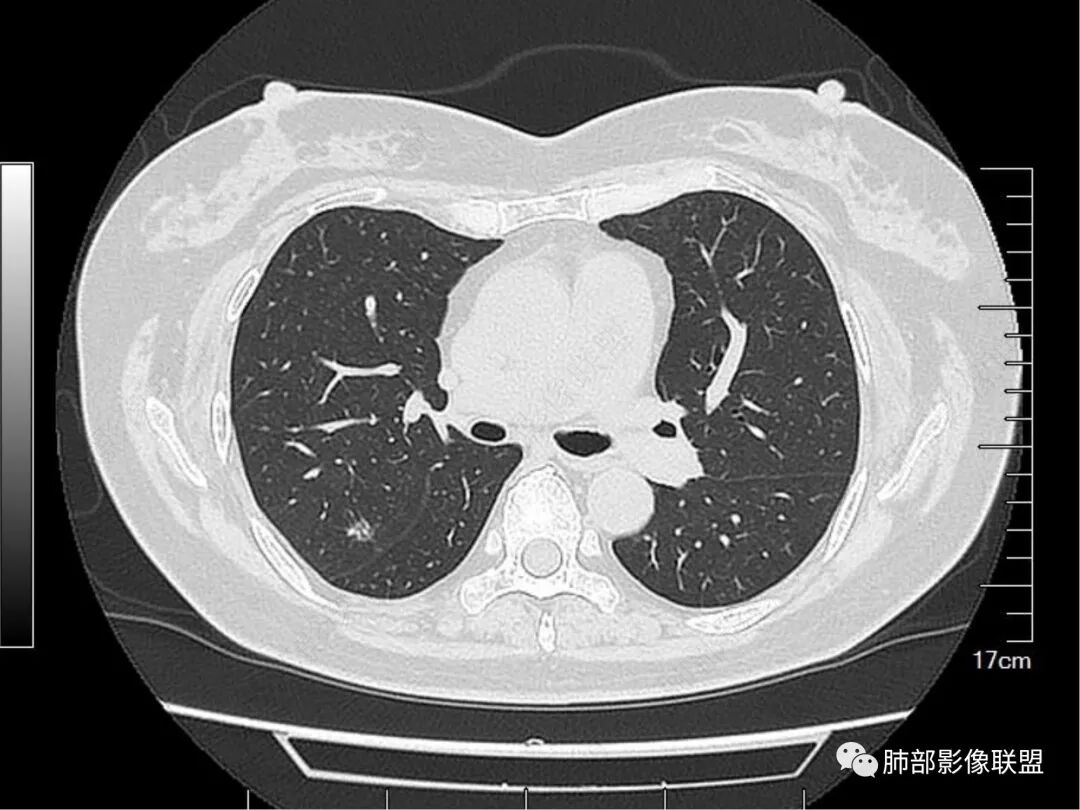

看完支气管我们继续看这个次级肺小叶的背景。

![]()

这里几乎是病灶的最上缘。明显是有丝丝拉拉的不干净的背景,与周围正常组织比较,很明确。

较中央的区域。明确的细网格,多发的。